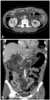

A gastroenterostomy is the surgical creation of a connection between the stomach and the jejunum. The operation can sometimes be performed at the same time as a partial gastrectomy (the removal of part of the stomach). [Source: Wikipedia ]